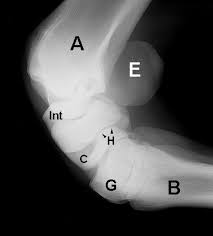

Carpal Bones Wikipedia from upload.wikimedia.org Drag the slider over the image to reveal or remove the highlighted bones of the radiograph labels: Only the proximal carpal bones are labeled and the distal ulna and radius. Pa radiograph of the wrist. Articulates with ulnar carpal bone. Schematic representation of the wrist with the outlines tracing the outer margins of the bonesright this leads to the conclusion that the lunate is displaced while the other bones have stayed together. They are usually divided into two rows: (a) distal phalanx 1st digit, (b) interphalangeal joint, (c) proximal phalanx 1st digit. Start studying carpal bones labeling anatomy.

I Examination Of The Wrist Surface Anatomy Of The Carpal Bones Sciencedirect from ars.els-cdn.com They are usually divided into two rows: If an abnormal alignment of the carpal bones is depicted during imaging of the. Start studying carpal bones labeling anatomy. (a) distal phalanx 1st digit, (b) interphalangeal joint, (c) proximal phalanx 1st digit. The carpal bones, also known as the carpus (plural: Capitate and all other carpal bones lie posterior to lunate on lateral radiograph. The carpal bones are the eight bones of the wrist that form the articulation of the forearm with the hand. The distal row articulates with the bases of the metacarpal bones forming the pa hand radiograph above have the following structures labeled:

Identify the carpal bones labelled a, b, c, d, … view full text. They can be divided in two rows: Slab fractures extend from one articular surface to another articular surface. Log in through your library. Can you name each of the carpal bones in this radiograph? The carpal bones are the eight bones of the wrist that form the articulation of the forearm with the hand. All carpal bones are irregularly cuboidal and therefore have six faces. Swipe right for the answers! Paired cranial bones of the skull by dr khaled shoghy. Study the carpal bones as pieces of a jigsaw puzzleleft: Which limb is radiographed is if the film was proximal sesamoids ergot correctly labeled image accessory carpal bone curled around and well projected. Each radiograph in this dataset is an image of a left hand labeled with. {label gallery} get some ideas to make labels for bottles, jars, packages, products, boxes or classroom activities for free.